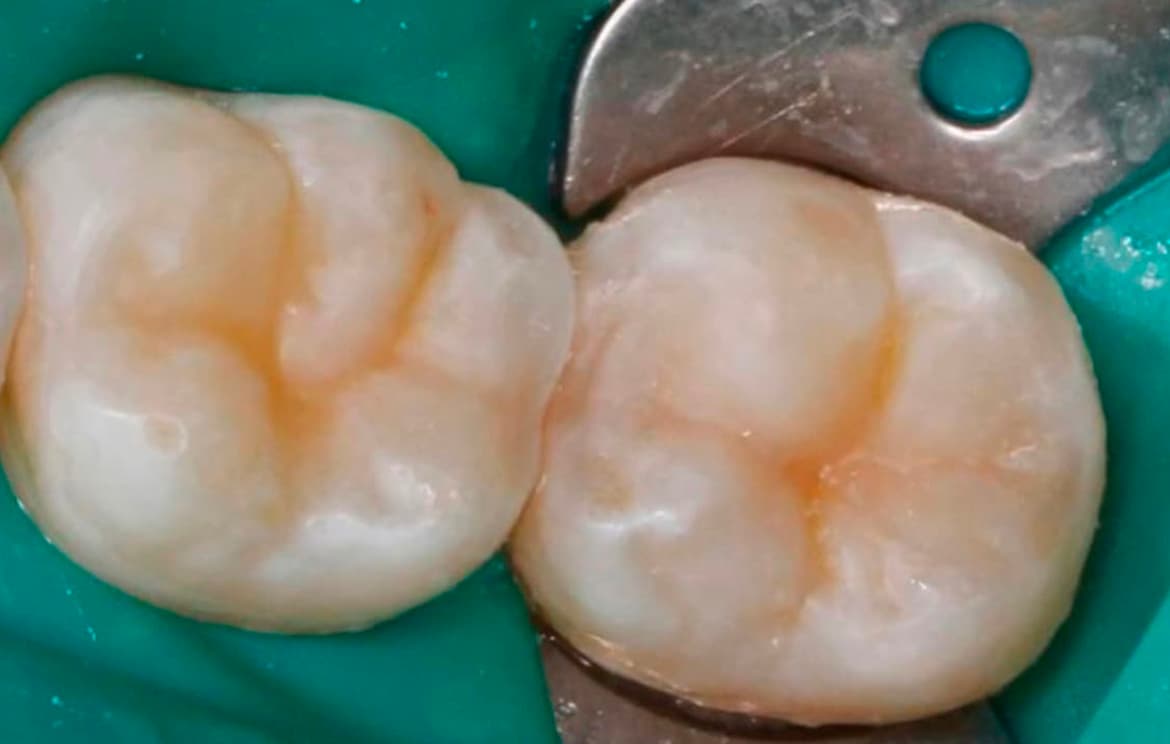

Наши работы